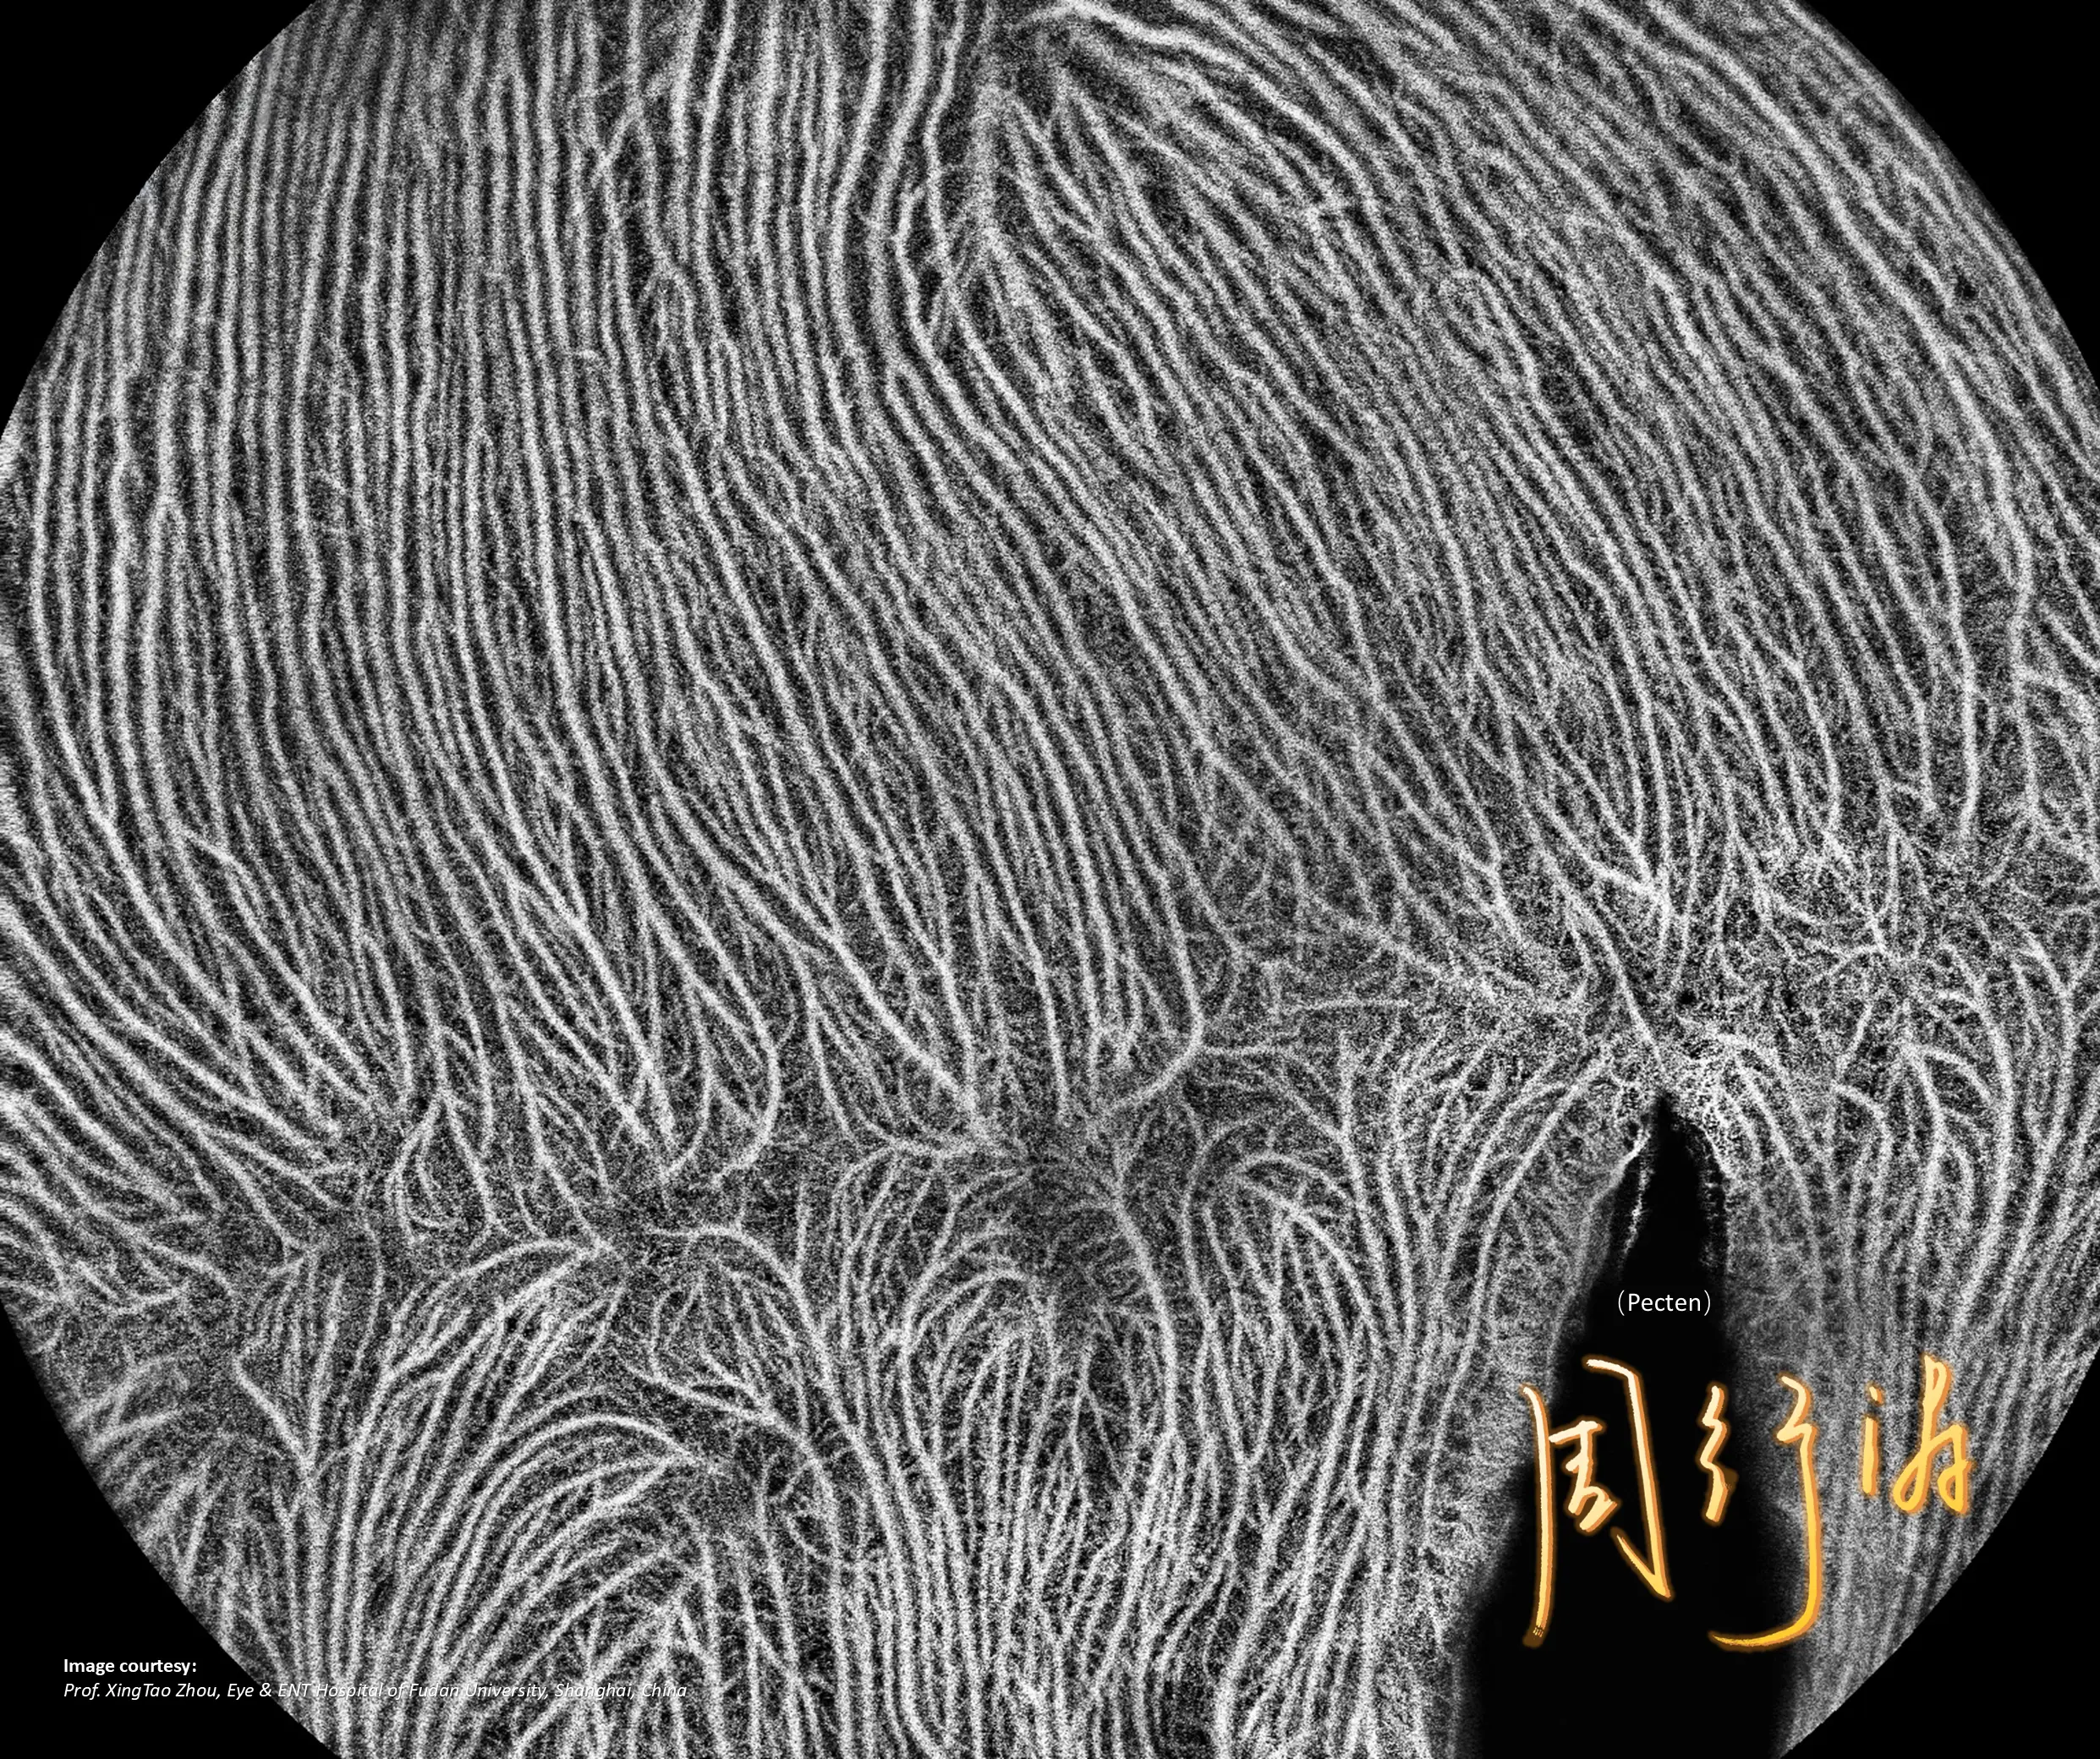

NIEZRÓWNANA JAKOŚĆ OBRAZOWANIA

Pełna diagnostyka

w jednym ujęciu

GALERIA PRZYPADKÓW

Kliniczne znaczenie

innowacji